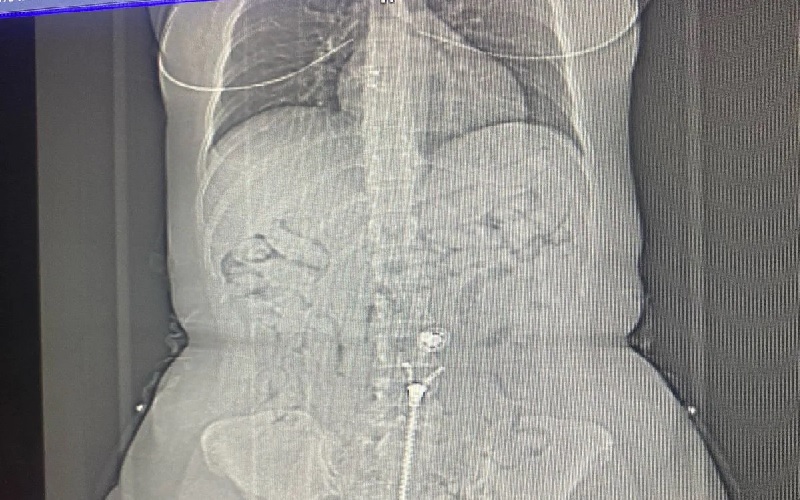

(Foto: Reprodução) – A Polícia Federal prendeu passageira com 100 cápsulas de cocaína no estômago em operação em Belém. Confira os detalhes.

As mulheres foram retiradas do voo em Belém, por volta de 00h30 deste domingo. Em revista pessoal foram encontradas oito cápsulas de cocaína nos sapatos e dentro da roupa da brasileira. Se sentindo enferma, ela confessou ter cerca de 80 outras cápsulas no estômago, sendo conduzida até a emergência do Hospital Metropolitano de Belém, para expelir as demais cápsulas. Foram apreendidos 500 euros em posse da brasileira.